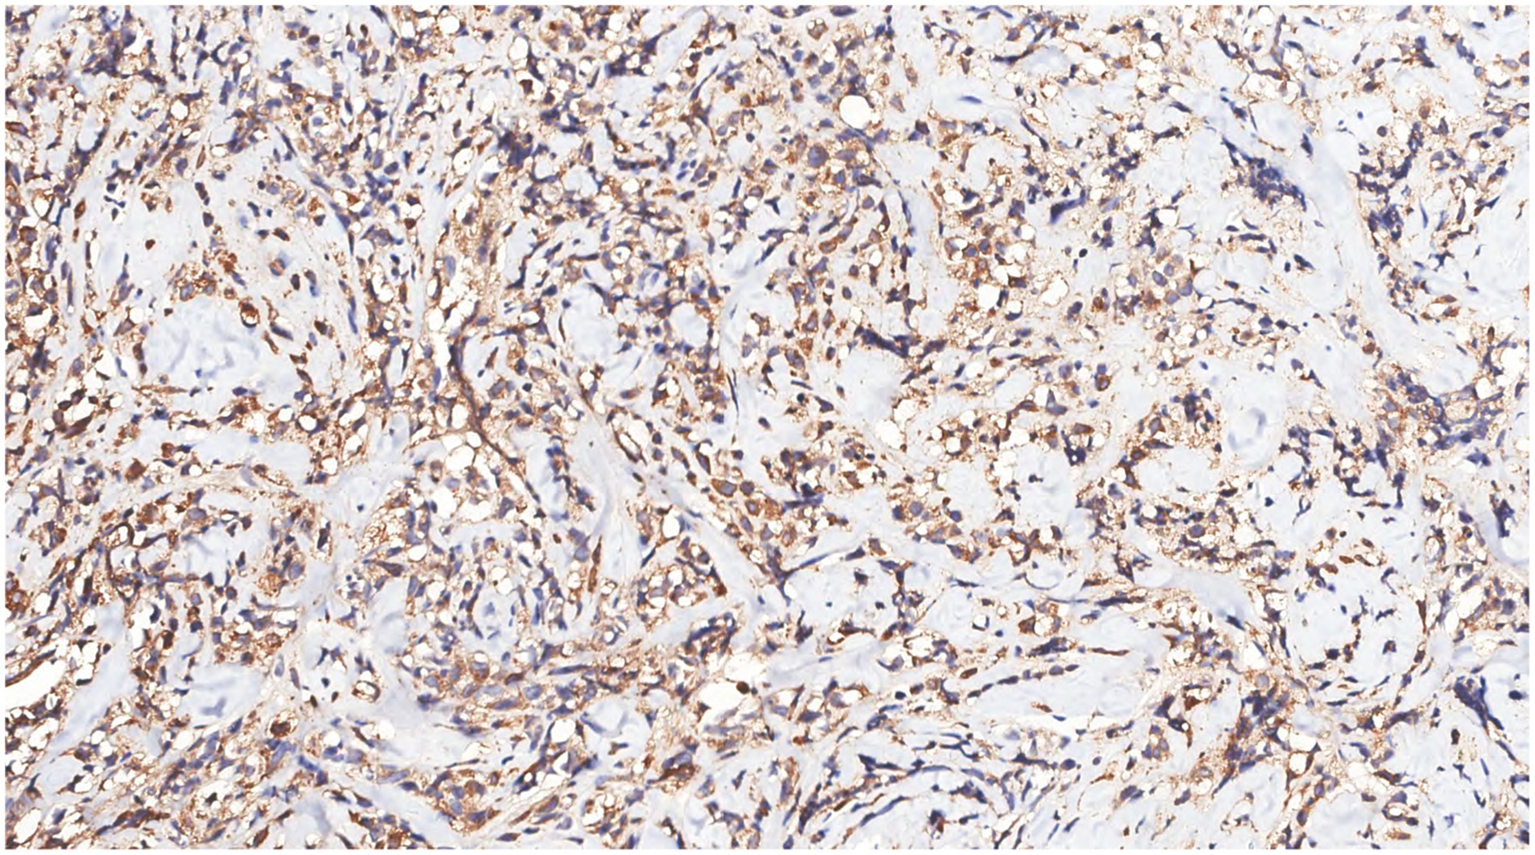

Immunohistochemical analysis of tumor cells revealed the following: Vimentin (+), LCA (+) (Figure 9), MPO (+) (Figure 10), CD68 (+) (Figure 11), CD117 (+) (Figure 12), CD15 (+) and CD123 (in +), CD34 (in +), CK (−), CD20 (−), CD3 (−), GATA3 (−), TRPS1 (−), and Ki-67 (70%+).

Figure 9

Immunohistochemistry showed LCA(+) of tumor cells.

Figure 11

Immunohistochemistry showed that the tumor cells were CD68(+).